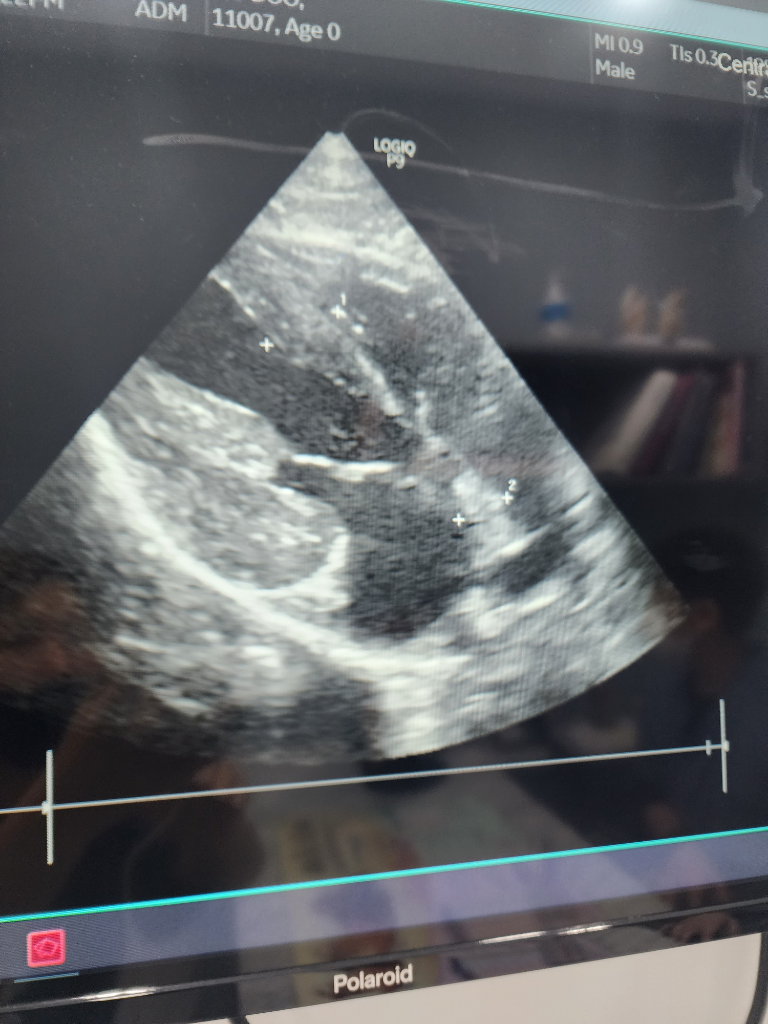

다음날 심장초음파검사로 hcm확정, 분당 60회 호흡과 혈전후지마비증상만 있습니다.